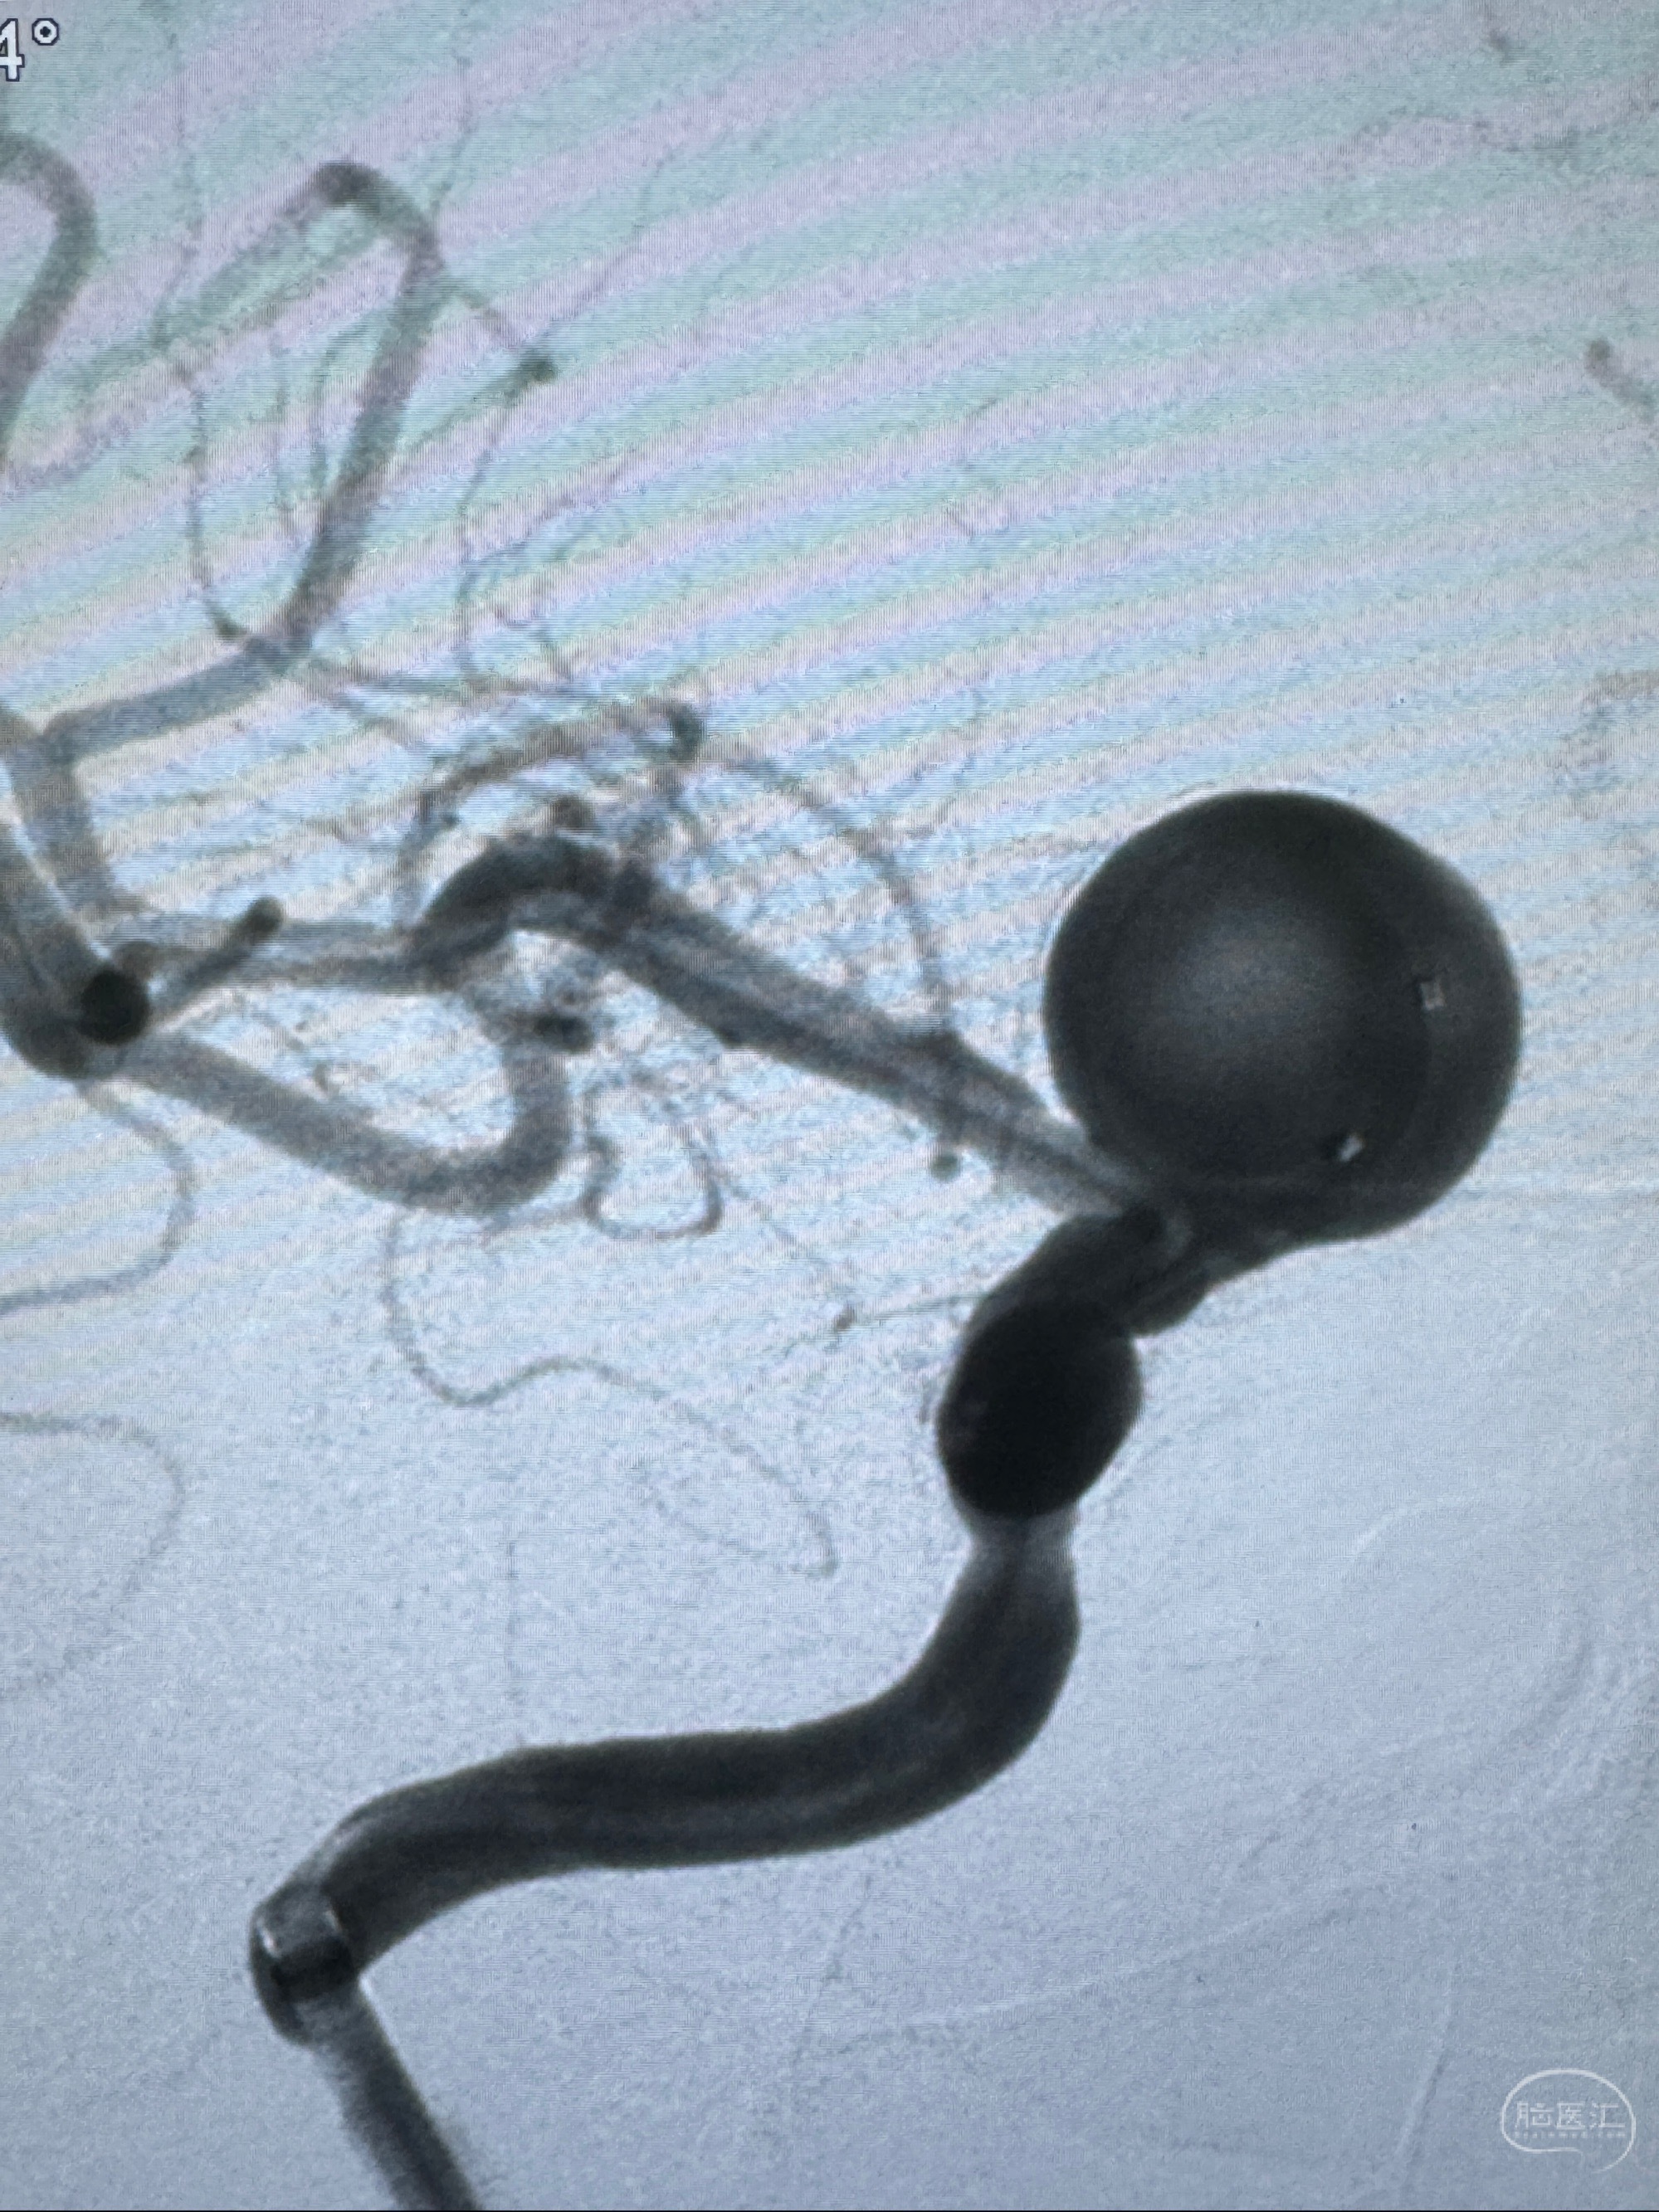

2023-12-27术后第十天复查DSA

支架贴壁佳,但可见射流,咋办?

2024-01-08全麻下再行植入密网支架一枚

Tubridge 4.5-35mm

支架植入顺利,贴壁佳,支架内血流通畅,动脉瘤内血液滞留明显